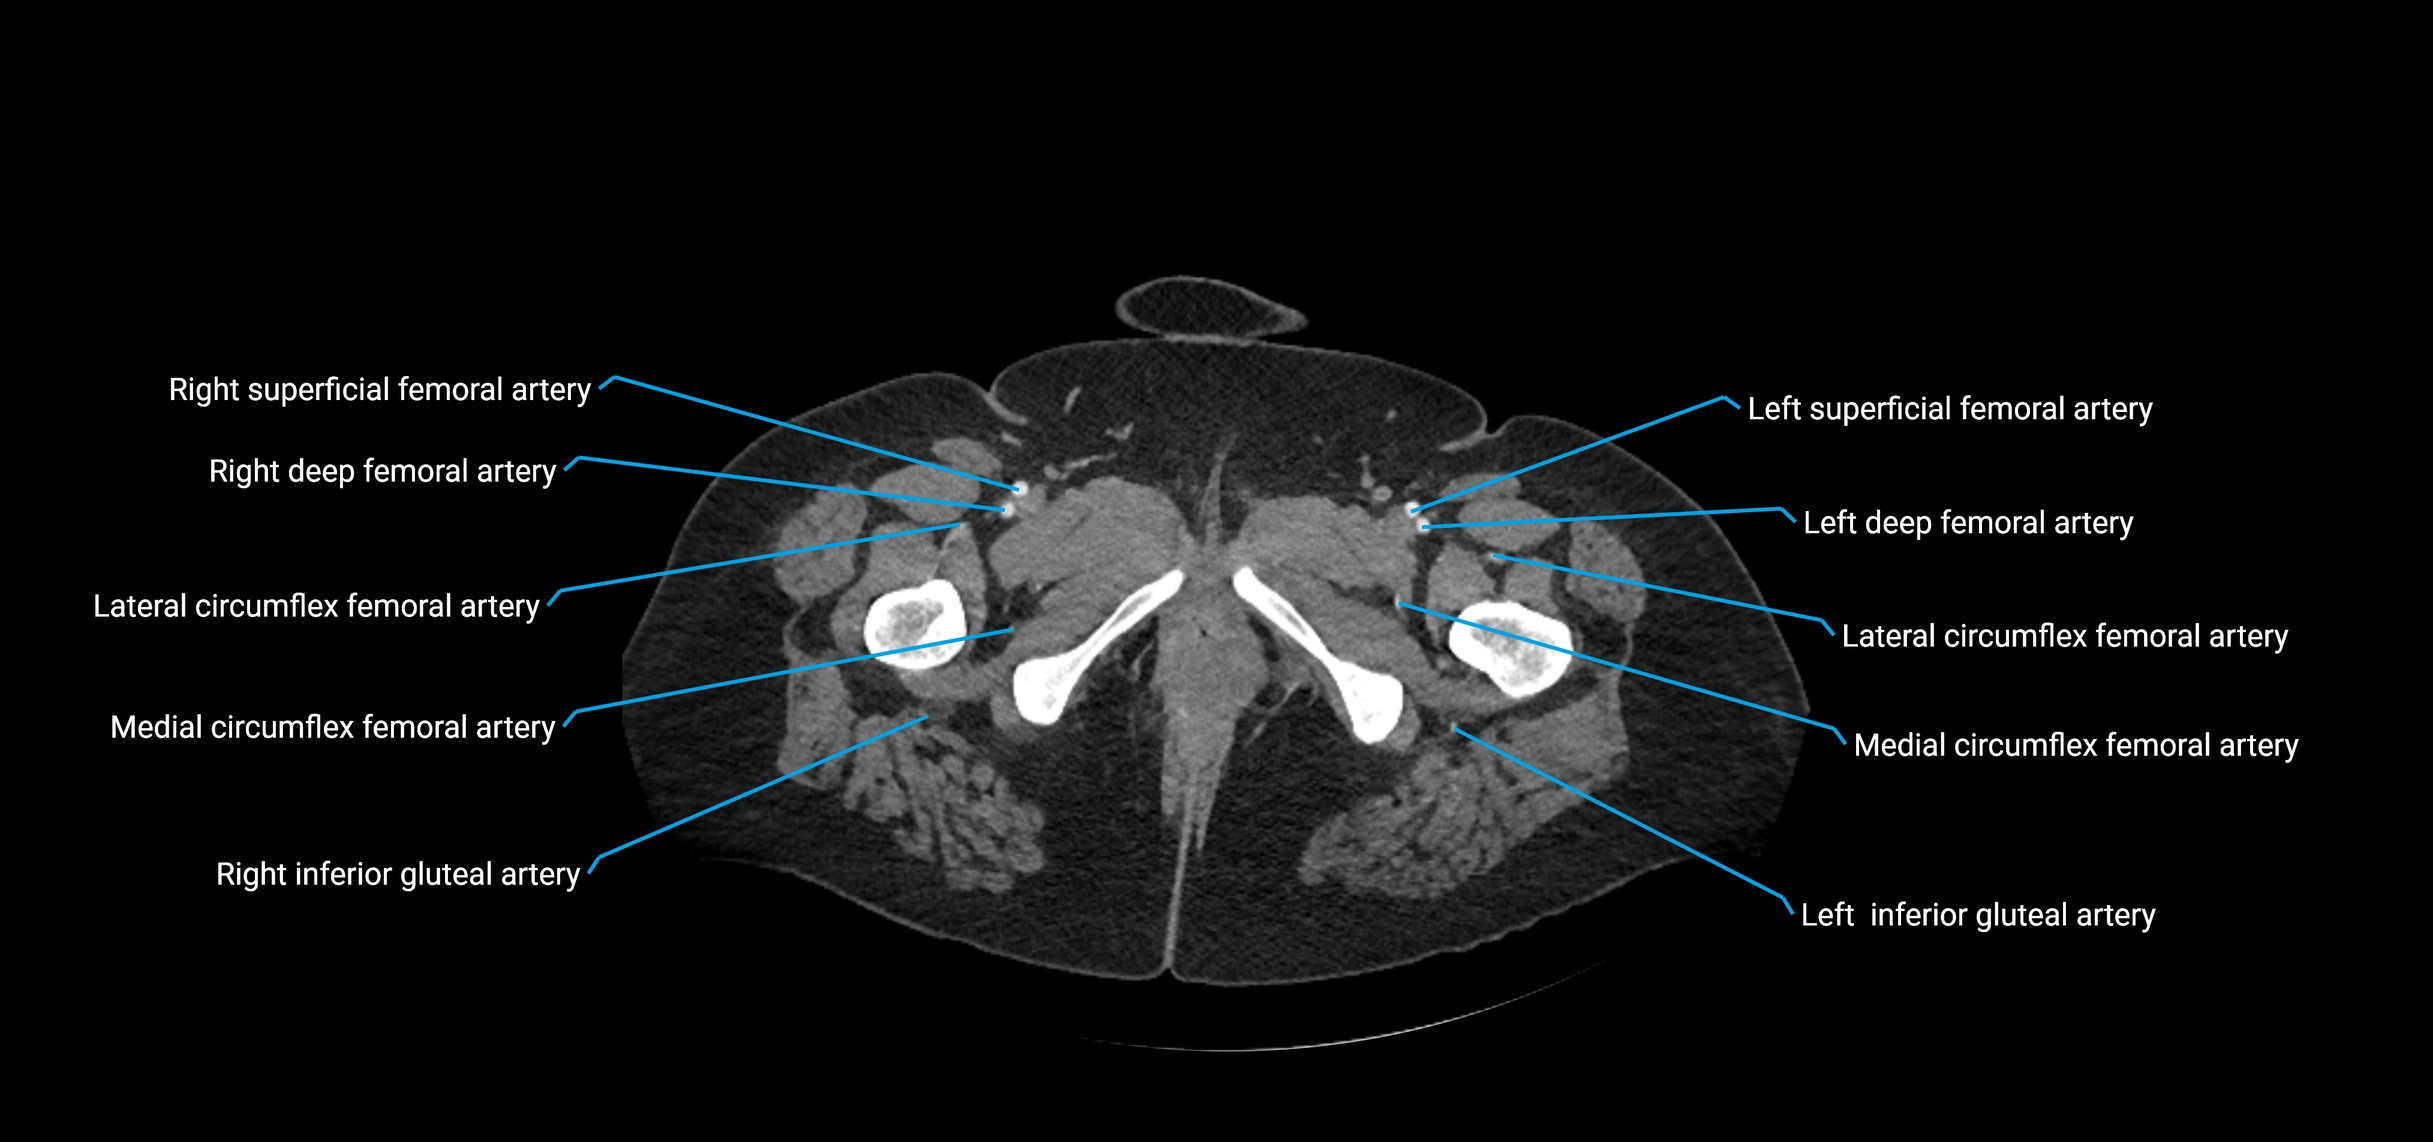

CT Appearance

Non-contrast CT:

• Appears as a tubular soft tissue structure anterior to vertebral bodies

• Calcified atherosclerotic plaques appear as hyperdense foci along the wall

• Useful for screening abdominal aortic aneurysm (AAA) size and mural calcification

Contrast-enhanced CT (CTA):

• Gold standard for abdominal aortic imaging

• Provides excellent detail of lumen, wall, aneurysm, thrombus, and branch vessels

• Multiplanar and 3D reconstructions help in aneurysm measurement, stent graft planning, and dissection evaluation

• Detects acute rupture, traumatic injury, or occlusion with high sensitivity

CT images

image